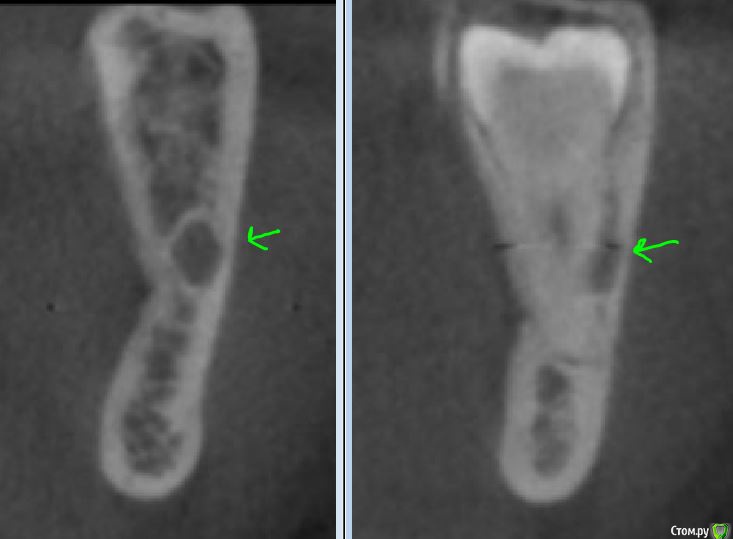

Alena.vsk Опубликовано 30 июля, 2016 Поделиться Опубликовано 30 июля, 2016 (изменено) Здравствуйте, уважаемые специалисты и посетители форума! 4 недели назад был удален 38й зубик. Хирург изначально до операции сделал панораму и 3д томограмму, чтобы понять как проходит нерв, и сообщил, что в моем случае крайне вероятно (99%) возникновение парастезии, до полугода. Т.к. нерв раздавлен зубом, и удалить зуб, не задев нерв, практически невозможно.Удалили относительно быстро: на всё не больше часа, включая уколы и разговоры.Доктор напоследок осмотрел лунку, хотел понять видно ли визуально нерв.В итоге сказал что нерв не виден, остался доволен и уже оценив результат, сообщил что вполне возможно парастезия меня обойдет стороной.Но увы, не обошла: подбородок и нижняя губа онемевшие. Язык и десна - в норме. Заживление в целом проходило и проходит нормально, не считая долго сходившего отека (около 10 дней), но это скорее моя склонность к отекам. Первые дней 10:-очень ломило 31-33 зубы + сильная чувствительность. ПРиходилось пить обезбаливающее.-Подбородок не чувствовал практически ничего. Только при сильном прикосновении чувствовались какие-то оооочень далекие ощущения, даже не похожие на прикосновения. Можно сказать, около 3% чувствительности, и то какой-то не правильной.- нижняя губа первые 10 дней была чуууточку более чувствительна, чем подбородок. Но вместо прикосновений - ощущала только жжение. И даже если губу не трогать - жгло почти постоянно. На сегодня (4 недели после удаления):-Боль 31-33их зубов полностью прошла.-Жжение нижней губы стало намного слабее, но пока слегка сохраняется, и только при мимике и прикосновении. -Подбородок по прежднему "мертвый", подвижек никаких по сравнению с первыми днями. Чувствует только температуру: холодное чувствует хорошо, горячее плохо, только если сочень горячее прикладывать. Изредка чешется, чем доставляет мучения, т.к. "прочесать" зудящее место невозможно. Но кажется (надеюсь не кажется), в кайме губы появилось легкое ощущение чувствительности, похожее на правильное нормальное ощущение. Но только в кайме. В толще губы по прежднему только жжение при прикосновении. с 20ого дня после удаления начала принимать: 1 таб Мильгаммы утром, 1 таб Нейромультивит вечером (по рекомендации хирурга) Собственно ВОПРОС Подбородок и губа- это одна и та же ветка нерва? Можно ли считать, что раз в кайме губы появилась какая-то слабая чувствительность - то значит нерв не перебит совсем и подбородок с толщей губы тоже теперь гарантированно восстановятся?Или же это разные ветки нерва, и если кайма восстановилась, то не факт что восстановится и все остальное? На всякий случай прикладываю рентген и томограмму до, и рентген после. Хирург у меня хороший, пошла к нему по рекомендации от 4х друзей, но очень уж неразговорчивый. На все мои вопросы отвечал "время покажет", давал назначения, промывал лунку и быстренько выпроваживал.Сейчас он на несколько недель в отъезде. И еще один ВОПРОС! По рентгену "после" можно понять, нормально ли затягивается лунка костной тканью? Визуально оценить не могу, т.к. десну зашивали частично, оставлен только разрез между щекой и зубами (разрез по прежднему есть, пока не заживает). Рентген сделан сегодня, т.е. лунке уже месяц. ДО ПОСЛЕ Изменено 30 июля, 2016 пользователем Alena.vsk Ссылка на комментарий